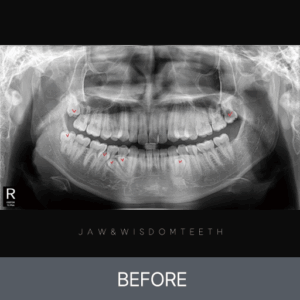

턱관절 CASE